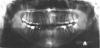

persona Опубликовано 12 октября, 2008 Поделиться Опубликовано 12 октября, 2008 (изменено) Здравствуйте.Хочу спросить совета у специалистов.Мне 25 лет. Решил разобраться со своими кривыми зубами. Пытался и раньше, но то, что мне сделали с помощью обычной пластинки еще в школьные годы, уже давно разъехалось в разные стороны. Мой случай в чем то, наверное, похож на вот этот:http://forum.stom.ru/index.php?showtopic=3286, только у меня все еще более запущено.Основная проблема в том, что у меня не вырос левый клык. Он остался внутри и лежит горизонтально. В результате, все верхние резцы съехали на свободное место, появились большие щели. Левая двойка даже умудрилась заехать за нижний клык. На нижней челюсти зубы скученны, что конечно тоже хотелось бы исправить. Был у разных врачей. Насколько я понял, в моем случае желательно использовать брэкеты Damon. Предлагают две стратегии лечения:1) Освобождать место в зоне невышедшего клыка, а затем либо вытягивать его (что маловероятно), либо удалять клык и вставлять имплант на это место. При этом верхние резцы выдвинутся немного вперед и, соответственно, освободится место для выправления нижних зубов без удаления.2) Невышедший клык не трогаем, на его место смещается 4-ка, которая и будет исполнять роль этого клыка. Верхние зубы смещаются к центру, а нижние выпрямляются с удалением левой 4-ки. Последний из посещенных мною врачей как раз предлагает 2-ой подход, а про 1-ый говорит, что на такое лечение уйдет больше времени + придется удалять невышедший клык, без чего можно вполне обойтись + с недоверием относится к выдвижению верхних зубов + наверняка придется удалять какие-то 8-ки + выглядеть все в итоге будет примерно также. Но врач, который предлагал 1-ый способ, тоже вроде опытный специалист, так что я не знаю, кому из них больше доверять. Прошу знающих людей помочь мне определиться с методом лечения, да и вообще поделиться какими-то своими соображениями по поводу моего случая. Выкладываю фотографии и панорамный снимок. На фото верхней челюсти не жвачка , а временная пломба - сейчас как раз прохожу лечение у стоматолога, так что не обращайте внимание. Изменено 12 октября, 2008 пользователем persona Ссылка на комментарий

persona Опубликовано 12 октября, 2008 Автор Поделиться Опубликовано 12 октября, 2008 (изменено) Кроме того, проходил КТ. Выкладываю несколько срезов в области клыка. Изменено 12 октября, 2008 пользователем persona Ссылка на комментарий

Премоляр Опубликовано 14 октября, 2008 Поделиться Опубликовано 14 октября, 2008 Хм, честно говоря, у меня тоже небольшие сомнения вызывала возможность отцентровки при таком лечении.Т.е. вы за вариант лечения с имплантом? Но в этом случае точно придется удалять ретинированный клык, а при 2-ом плане лечения его можно было бы не трогать.Поставить в зубную дугу ретенир.клык будет очень очень травматично и сложно.И оставлять "просто так" клык тоже нельзя-т.к. со временем вокруг клыка может образоваться киста.(а может и нет...). Возможно целесообразнее удалить нижнюю 4ку справа(коррекция центра) и выравнивание зубов на вер.чел+последующая реставрация 4 ки сверху справа. И еще-сделать КТ для определения точной локализации ретенир.зуба(решения вопроса о его дальнейшей судьбе) Ссылка на комментарий

persona Опубликовано 14 октября, 2008 Автор Поделиться Опубликовано 14 октября, 2008 Поставить в зубную дугу ретенир.клык будет очень очень травматично и сложно.И оставлять "просто так" клык тоже нельзя-т.к. со временем вокруг клыка может образоваться киста.(а может и нет...). Возможно целесообразнее удалить нижнюю 4ку справа(коррекция центра) и выравнивание зубов на вер.чел+последующая реставрация 4 ки сверху справа. И еще-сделать КТ для определения точной локализации ретенир.зуба(решения вопроса о его дальнейшей судьбе)Спасибо большое за ответ. Только я не совсем понял насчет 4-ок. Может имелись в виду не правые, а левые 4-ки? Если так, то это получится в точности 2-ой вариант из тех, что я написал в первом посте. Ретинированный клык все врачи кроме одного рекомендуют не трогать, т.к. пока не беспокоит и корней других зубов вроде не задевает. КТ я сделал. Несколько срезов выложены во 2-ом посте. Если надо, могу выложить еще, но они все горизонтальные. Также есть еще снимок с 3-мерным изображением, но не думаю, что там лучше видно. Ссылка на комментарий